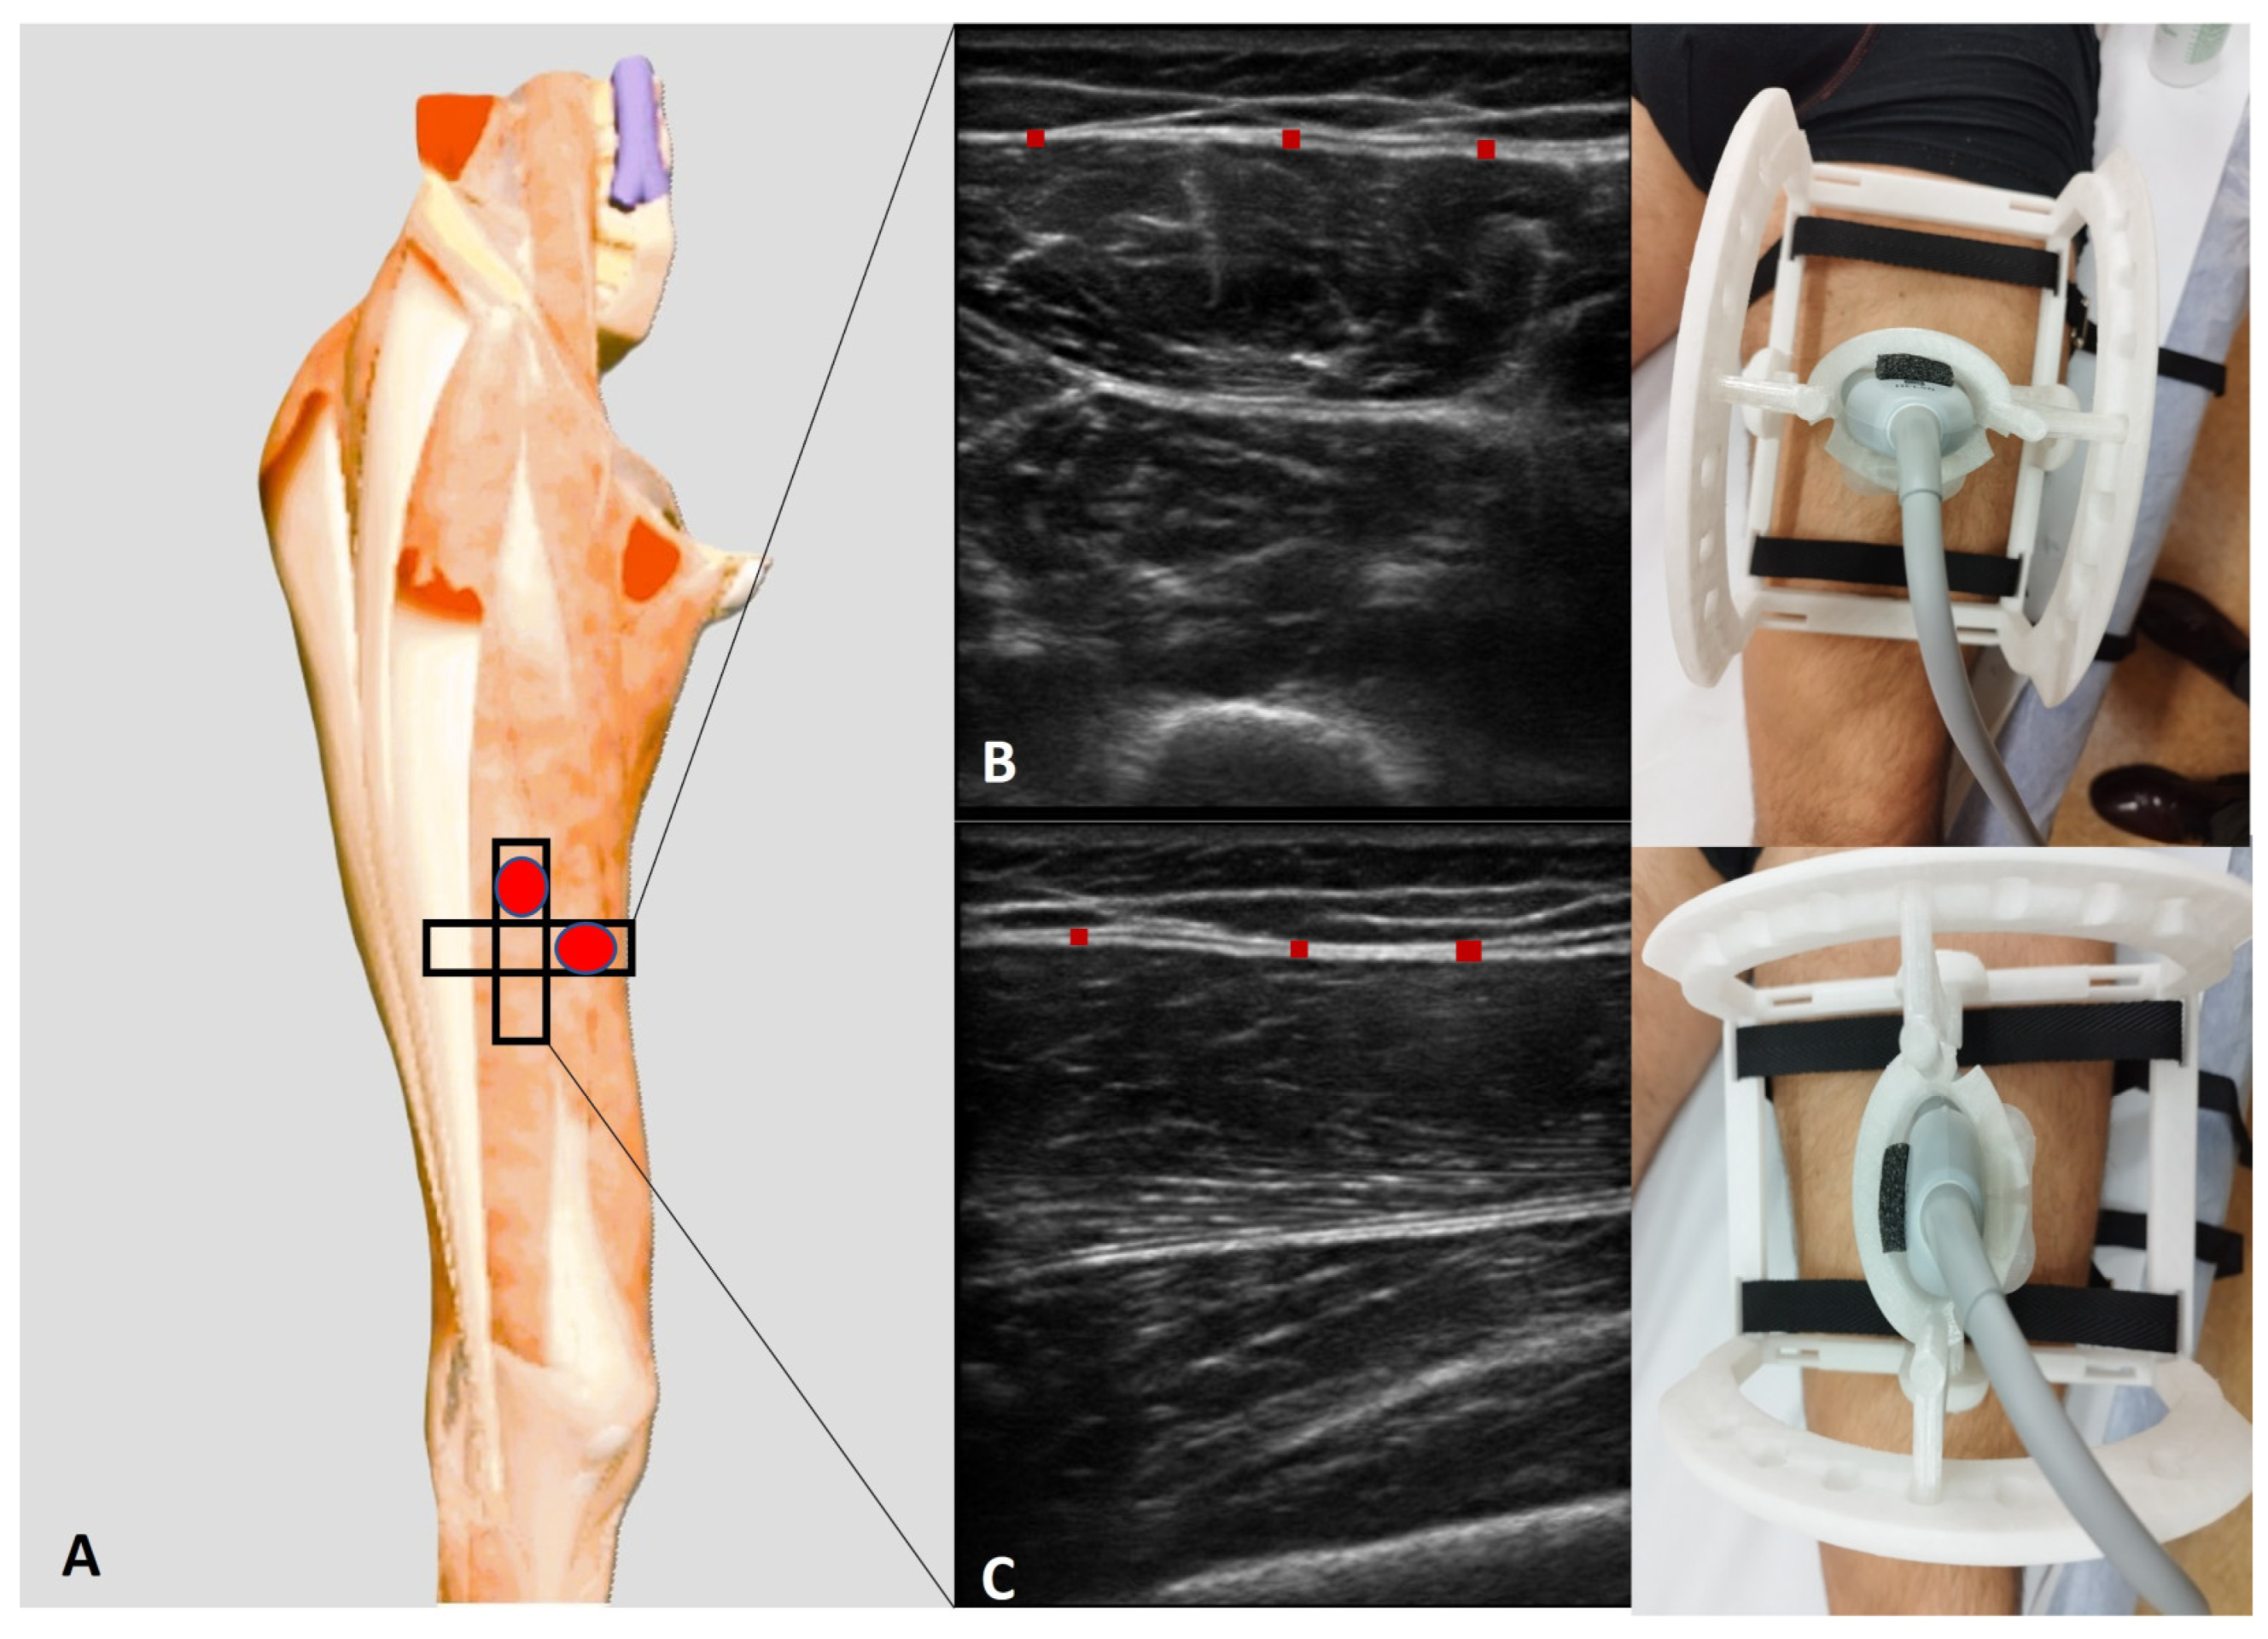

Employing an advanced high-resolution US machine (Edge II, Sonosite, FUJIFILM, Inc., Washington, WA, USA) with a frequency range of 6–15 MHz and a screen resolution of 1680 × 1050 pixels, US examination was performed at precise anatomical landmarks at the anterior region of the thigh. Furthermore, the anterior region of deep fascia of thigh was assessed following the protocol described by Pirri et al. [10]:

-

Ant 2 (transversal): With the volunteer in a relaxed supine position and the right lower limb in a neutral posture, the probe was placed at the Ant 1 scanning position [10] and further moved distally along the femur. The movement followed the alignment of the rectus femoris and vastus intermedius muscles, maintaining an axial/transversal orientation. As the probe advanced, the sartorius muscle progressively disappeared from the medial aspect of the US image. At this level, the vastus medialis appeared medially, while the vastus lateralis became visible laterally, delineating the transition in muscle architecture.

Ant 2 (longitudinal): For the longitudinal scan, the probe was rotated 90° to obtain a longitudinal view of the rectus femoris and vastus intermedius muscles. In this orientation, the rectus femoris appeared as a fusiform structure overlying the vastus intermedius, with its fibrous central tendon running parallel to the muscle fibers (Figure 2).

Figure 2. (A) Ultrasound protocol for performing anisotropy assessment of deep fascia. (B) Transversal scan (short axis). (C) Longitudinal scan (long axis). Red rectangle: deep fascia.